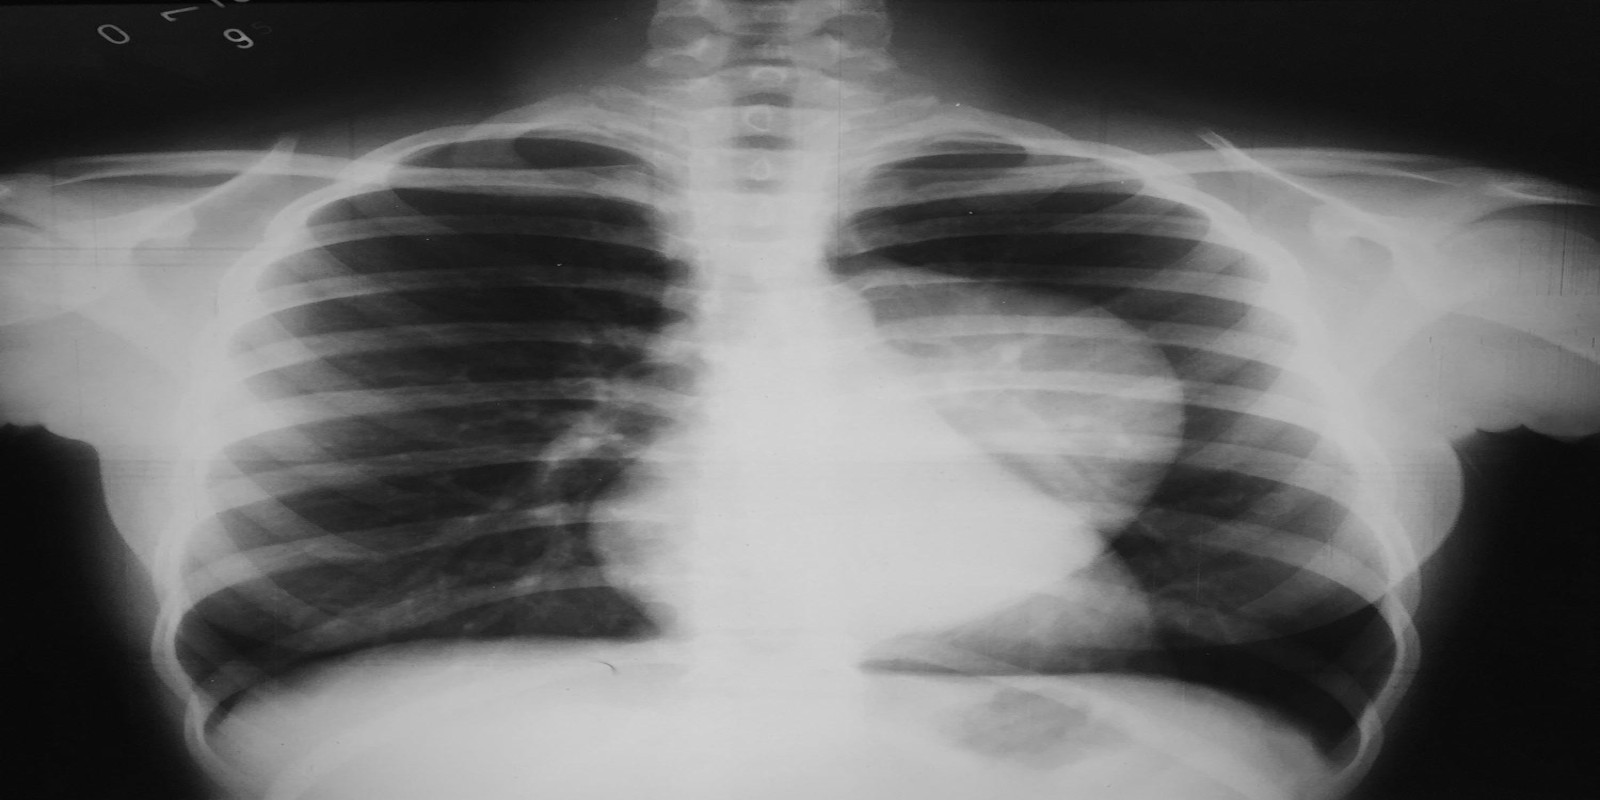

Ganglioneuroma mediastinal

Mediastinal Ganglioneuroma